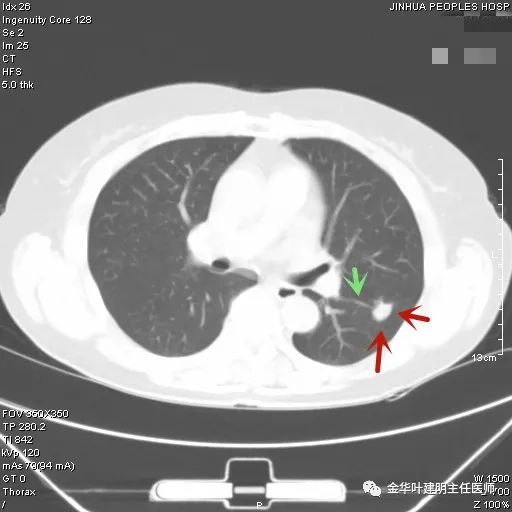

上图示结核。我们发现其有明显的卫星灶,如绿色箭头所示,主病灶处也是周边有模糊区域,病灶整体密度较为均匀(肿瘤容易生长不均致密度欠均匀,显杂乱)。